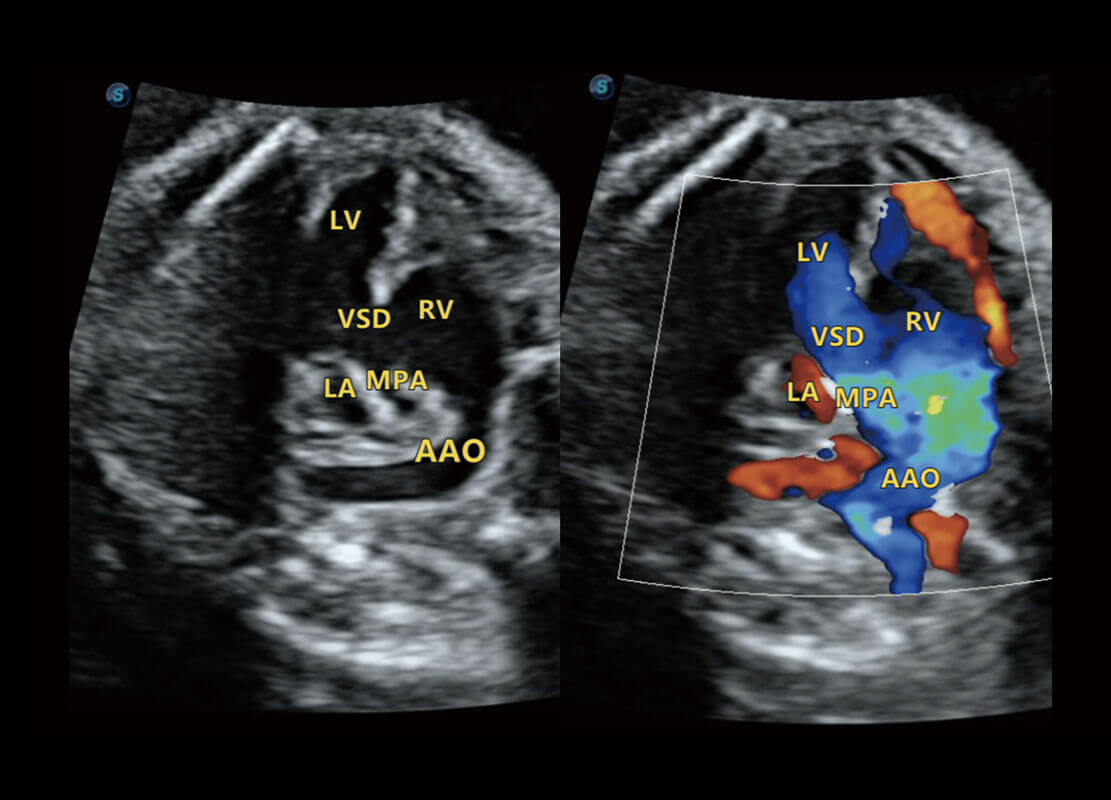

胎心筛查

P60搭载一系列胎儿心脏成像技术,实现精细的胎儿心脏评估。

• 四腔切面

• 四腔心血流

• 右室双出口

• 胎心容积成像